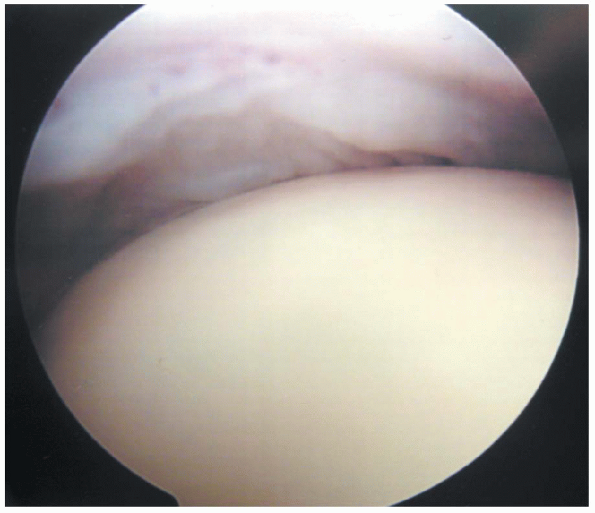

FIGURE 1-24.

View from the posterior portal. Abduction and internal rotation of the arm while the camera is directed posteriorly can allow for full visualization of the insertions of all of the rotator cuff tendons. It is important to be able to visualize the entire insertion to adequately assess the extent of any evident tears. |

The supraspinatus insertion can be identified just posterior to the

bicipital groove and followed posteriorly by abducting the arm while

rotating the arthroscope posteriorly (Fig. 1-23). This can allow for complete visualization of the insertions of the infraspinatus and teres minor (Fig. 1-24).

The posterosuperior aspect of the humeral head should be examined in

this position to document the presence or absence of a Hill Sachs

lesion.